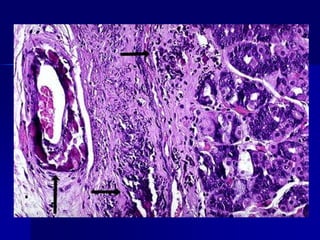

HIALINOSIS

DEGENERACIÓN HIALINA

 Término histológico descriptivo de lesión celular,

proporciona un aspecto homogéneo, vítreo y rosado

a las secciones histológicas rutinarias teñidas con

hematoxilina y eosina.

 En la hipertensión de larga duración y en la

diabetes mellitus, las paredes de las arteriolas,

especialmente en el riñón, se hialinizan, debido a la

proteína plasmática extravasada y al depósito de

material en la membrana basal.

DEGENERACIÓN HIALINA  Términohistológico descriptivo de lesión celular, proporciona un aspecto homogéneo, vítreo y rosado a las secciones histológicas rutinarias teñidas con hematoxilina y eosina.

• 83.

 En lahipertensión de larga duración y en la diabetes mellitus, las paredes de las arteriolas, especialmente en el riñón, se hialinizan, debido a la proteína plasmática extravasada y al depósito de material en la membrana basal.